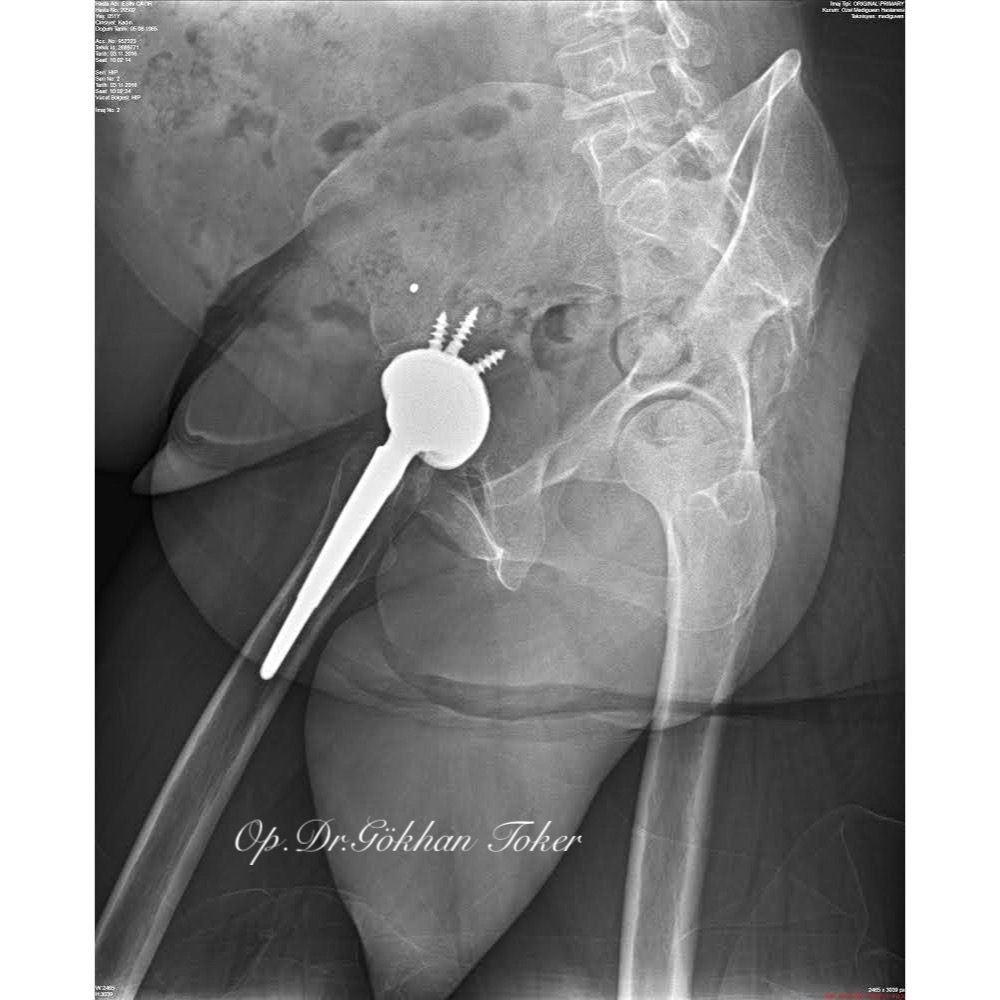

E.C.